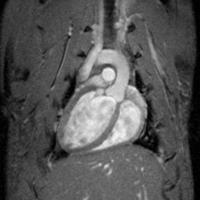

Using positron-emission tomography (PET)/computed tomography (CT) and magnetic resonance imaging (MRI), the research team showed that dalcetrapib, a novel treatment for atherosclerosis, prevented the progression of disease and reduced vascular inflammation; the results were noted over 24 months. The data are published in the September 12 issue of The Lancet.

The dal-PLAQUE study is the longest placebo-controlled, active-drug MRI study to date, and the first to use a variety of noninvasive imaging techniques to visualize arterial plaque.

In this Phase IIB, double-blind, multicenter trial, Mount Sinai researchers evaluated 130 study participants with atherosclerosis randomized to receive dalcetrapib or placebo for 24 months. To determine efficacy, the team used MRI to analyze plaque progression in the arterial wall and PET/CT to assess arterial inflammation. The images showed dalcetrapib significantly reduced atherosclerotic disease progression and inflammation.

In the dal-PLAQUE study, patients who received dalcetrapib saw a 31 percent increase in HDL cholesterol levels, as examined through MRI. The PET/CT scans showed inflammation levels in the carotid artery of those same patients were significantly reduced, yet stayed the same in the placebo group.